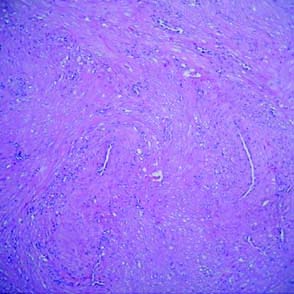

La exéresis fue completa con márgenes suficientes. Macroscópicamente se evidenció una tumoración de 1.4 por 0.8 por 0.6 de color blanquecino, consistencia elástica, y con un área sólida blanquecina de mayor consistencia de 0.7 por 0.5cm. (Fig. 4).El examen microscópico mostró proliferación de células fusiformes sin atipía, dispuestas en haces y rodeando estructuras vasculares de paredes gruesas. Resultando positiva la inmuno marcación para actina muscular específica y CD 34 para endotelio, se concluye el diagnóstico angioleiomioma.(Fig 5,6 y 7)

Figura 5: Proliferación de fibras musculares lisas asociadas a vasos de grueso calibre. (H-E)

Figura 6: Inmunomarcación para actina muscular especifica

Figura 7: Inmunomarcación con CD 34 para endotelios.